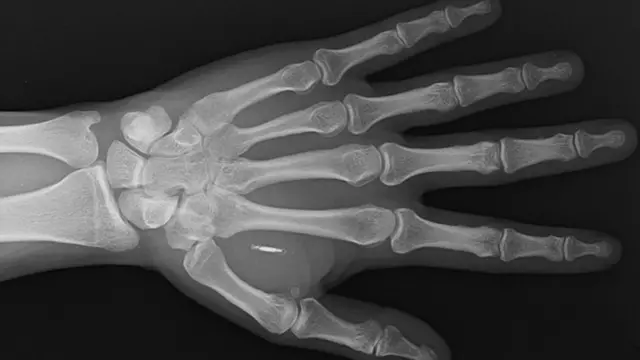

Ọgbẹni Paumen le ṣe eyi, nitori pe o fi ẹrọ kan, 'microchip', to le san owo sinu agọ ara rẹ ni ọdun 2019.

Abẹ awọ to wa ni ọwọ osi rẹ ni wọn fi ẹrọ naa pamọ si, eyi to ma n tan ina nigba to ba sunmọ ẹrọ to n gba owo, bii POS.

- Kaadi microchip yii gbọdọ sunmọ ẹrọ to ni 'electromagnetic' ko to o le ṣiṣẹ. Imọ ẹrọ naa ni yoo rin kaakiri gbogbo ara eniyan lati ṣawari RFID chip implant yii.